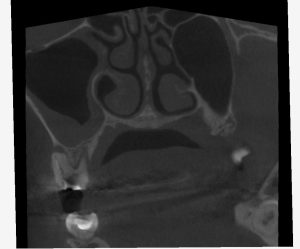

レントゲンを見てみよう。

(術前レントゲン、CT)

全ての根管に、根尖病変が存在する。

打診(+)、咬合痛(+)の状態であった。